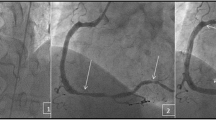

In the era of COVID-19, cardiovascular diseases and cancer remain the leading causes of mortality in the USA [1, 2]. Due to a combination of shared risk factors, improved life span, and advancement in cancer therapies, there is a growing number of cancer patients with coexisting coronary artery disease (CAD) [3]. Cancer and its treatment can be associated in selected cases with additional vascular aging [4]. Despite increased prevalence, cancer patients are still routinely excluded from major cardiovascular randomized control trials. In recent years, several observational studies have helped us understand the pathophysiology and treatment principles needed to tailor management in such a high-risk population. The purpose of this review is to provide recent updates about the management of CAD in cancer patients, with a focus on discussing optimal strategies for coronary revascularization (Fig. 1).

Recent updates in coronary revascularization in cancer patients. ICI, immune checkpoint inhibitors; ACS, acute coronary syndrome; TTE, transthoracic echocardiogram; STEMI, ST segment elevation myocardial infarction; NSTEMI, non-ST segment elevation myocardial infarction; DAPT, dual antiplatelet therapy; FFR, fractional flow reserve; iFR, instantaneous wave-free ratio; IVUS, intravascular ultrasound; OCT, optical coherence tomography; SADIT, single-access, dual-injection technique; SHiP, Single access for Hi-risk PCI; TEG, thromboelastogram; PCI, percutaneous coronary intervention.